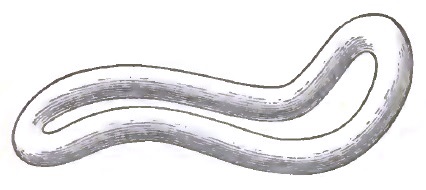

| 7. | THE EMMET CURVES (PESSARY) |

| 8. | THE ALBERT SMITH CURVES (PESSARY) |